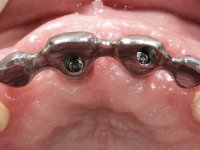

Primeira Fase

Foram feitas as extrações das raízes dos dentes 2.1 e 2.2 porque estavam a incomodar. Após 3 meses de cicatrização fez-se o exame imagiológico e estudo implantar para colocação do implante no local do 2.1.Foi colocado um implante de 4.1mm de diâmetro por 10mm de altura, colocado ao nível ósseo. Passados 2 meses após a cirurgia implantar, foi feita a segunda cirurgia para colocação de um parafuso de cicatrização. Foi feita a impressão ao implante com técnica de moldeira aberta com silicone de dupla viscosidade um mês após. No laboratório foi confecionada uma infraestrutura metálica para uma ponte de 2 elementos aparafusada ao implante. Esta infraestrutura apresentava 2 apoios palatinos para ajudar a estabilizar os dentes 1.1 e 2.3 a recuperar do traumatismo. Recuperados os dentes, os apoios poderiam ser retirados. Esta peça apresentava uma conexão interna ao implante com sistema anti-rotacional. A prova da infraestrutura foi feita em boca sendo o seu correto ajuste verificado com controle imagiológico. No revestimento da infraestrutura foi utilizada cerâmica de tonalidade coronária e gengival. Depois de verificada em boca e aprovada pelo paciente a ponte foi apertada definitivamente e o orifício de acesso obturado.